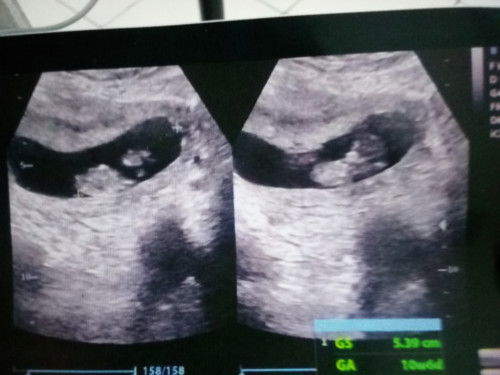

Kehamilan 10w6d seharusnya 8w4d

Assalamualaikum Mau bertanya apa ada keluhan seperti sya ini Pertama pas USG 5w3d dan udah ada kantung rahim, dan disuruh cek kembali sebulan kemudian, seharusnya klw dicek baru 8w4d, tapi pas di usg kata dokternya ini udah gede bayinya udah 10w 6h. Maaf ini apa yg salah ya. Padahal ini dari hasil usg

usia kehamilan 10 week udh gede blm bund janinnya di usg? udh trbentuk smw blm bund organnya?